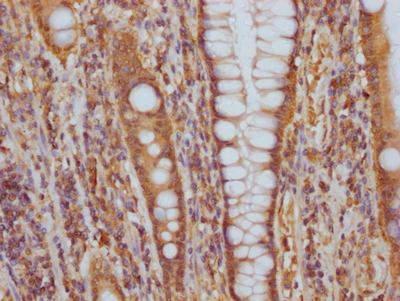

• IHC image of CSB-RA548303A0HU diluted at 1:100 and staining in paraffin-embedded human colon cancer performed on a Leica BondTM system. After dewaxing and hydration, antigen retrieval was mediated by high pressure in a citrate buffer (pH 6.0). Section was blocked with 10% normal goat serum 30min at RT. Then primary antibody (1% BSA) was incubated at 4℃ overnight. The primary is detected by a Goat anti-rabbit IgG polymer labeled by HRP and visualized using 0.05% DAB.